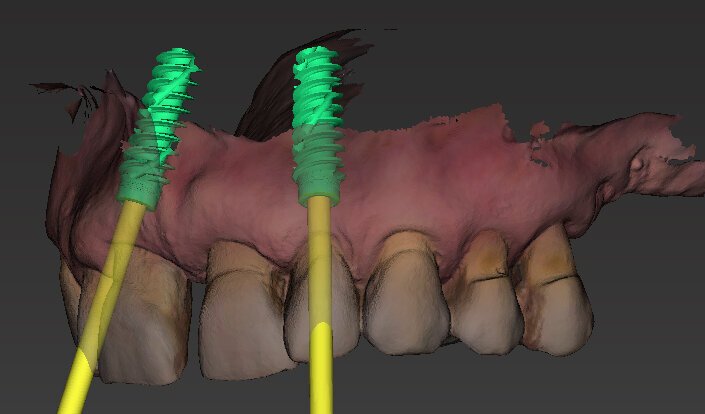

Il piano di trattamento prevede l’estrazione degli elementi dentali, l’inserimento di due impianti e la realizzazione di una protesi fissa di quattro elementi. Il problema da gestire è quello della fase provvisoria. Non è ipotizzabile una protesi mobile e quindi programmiamo di inserire subito dopo l’intervento un provvisorio immediato. Questo ci consente di condizionare da subito i tessuti periimplantari e anche le zone dei ponti. Si rileva un’impronta digitale (Figg. 5, 6), e la programmazione degli impianti viene effettuata con un software di chirurgia guidata (Fig. 7) e la posizione degli impianti nello spazio biologico e nello spazio protesico viene fatta sulla base di una ceratura diagnostica (Figg. 8, 9). Inseriamo gli impianti virtuali nell’osso disponibile (Figg. 10-13) e in relazione all’aspetto protesico correggiamo l’asse di inclinazione degli impianti con componenti secondarie angolate a 17° (Figg. 14, 15). Questo ci consentirà di realizzare una protesi avvitata con i fori situati nella zona palatale.

Il nostro obiettivo è quello di riuscire a dare alla paziente un provvisorio immediato nell’arco di due ore. Questo diventa possibile perché abbiamo utilizzato un flusso digitale fin dall’inizio. In laboratorio vengono realizzate la dima chirurgica (Figg. 16, 17), la dima protesica (Fig. 18) e anche il provvisorio (Figg. 19-21) che contiene delle alette di riposizionamento. Il tutto gestito con modelli digitali sui quali saremo in grado di funzionalizzare il provvisorio post-chirurgico (tecnica DIL). In un caso come questo se utilizziamo un flusso digitale possiamo evitare subito dopo la chirurgia di rilevare un’impronta degli impianti inseriti. Infatti, utilizziamo una dima chirurgica che ci faciliterà le fasi di intervento. La dima ci consentirà di non fare lembi e nessuna incisione di rilascio (Fig. 22), dopo aver inserito gli impianti (BLX Straumann) (Figg. 23-31) e aver controllato il loro alloggiamento, inseriamo sugli stessi dei transfert da impronta (Fig. 32).